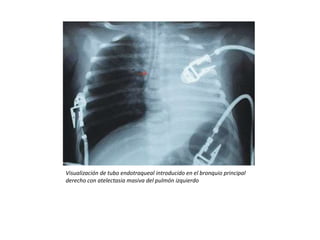

El documento proporciona información sobre diferentes aspectos relacionados con el aparato respiratorio y su cuidado. Describe varios procedimientos y patologías como la oxigenoterapia, ventilación mecánica no invasiva, neumotórax, atelectasia, asma y neumonía. También destaca la importancia de realizar ejercicio al aire libre y mantener una postura correcta para el adecuado desarrollo y funcionamiento del sistema respiratorio.